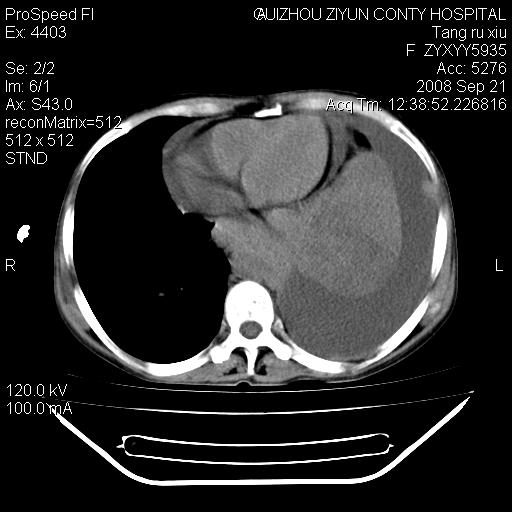

f、57岁,上腹痛.2月,近来胸闷。2月前在外院摄胸片示左侧胸腔少量积液。

(患者腹痛入院,欲吐,临床医生说禁饮,所以没有口服对比剂)

考虑----左侧胸腹腔积液----压迫性肺不张----心包积液---肝脏多发低密度影-----穿刺抽液后复查

左侧胸壁见一结节影,肝脏多发低密度影,左侧胸腔大量积液。建议增强

1)考虑左侧肺癌侵犯纵隔,左侧胸膜、肝脏及腹膜后淋巴结转移。2)左侧胸腔积液。3)心包积液。

肝脏大小形态尚可,其实质内可见多发大小不等的低密度影,边缘模糊。肝门区结构紊乱,腔静脉腹主动脉旁可见多发软组织密度影,部分融合成团块状,并向下延伸。胰腺及十二指肠结构显示不清。腹腔内脐后肠管走形僵硬,管壁可见增厚。盆腔内可见多个淋巴结影。所扫层面左侧胸腔可见大量弧形水样密度影,其内侧可见被压缩的肺组织影。左侧胸壁可见一小结节样软组织密度影,边缘模糊。心脏纵隔向右侧移位。心脏包膜内可见囊样低密度影,其内侧心房室周围可见一圈气体样密度影。纵隔内大血管旁可见多发软组织团块影,部分融合。

1.腹膜后淋巴瘤侵及肝脏,肺内及纵隔内多发转移。2.左侧大量胸腔积液并压缩性肺不张。3.心包脓肿可能,转移不除外。4.脐后局部肠管管壁增厚,考虑炎症可能,肿瘤不除外。